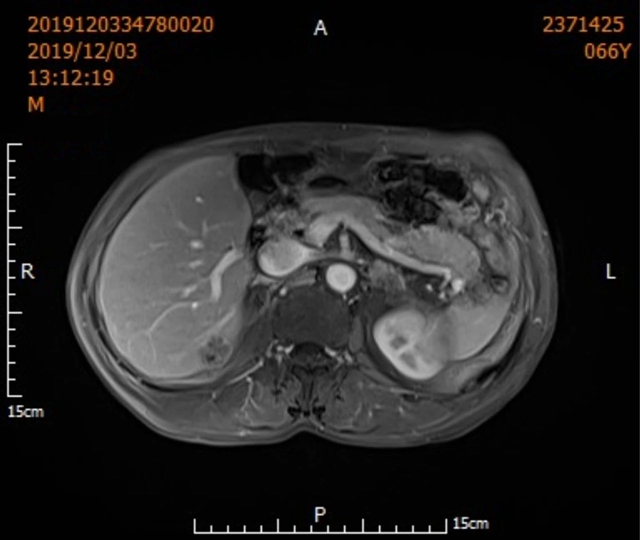

近日,辗转多地求医、均被拒之门外的王叔叔终于在泸州市人民医院拆下了他身上“巨型炸弹”,而这个“炸弹”的尺寸让人颇为惊讶...  一年多以前,51岁的王叔叔检查出身体内有不明包块。这个包块位于右侧胸腔和腹腔,分别约95cm、85cm。  后...